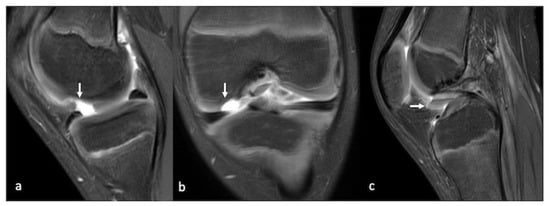

- Gorbachova, T.; Melenevsky, Y.; Cohen, M.; Cerniglia, B.W. Osteochondral Lesions of the Knee: Differentiating the Most Common Entities at MRI. Radiographics 2018, 38, 1478–1495. [Google Scholar] [CrossRef]

- Smet, A.A.D.; Ilahi, O.A.; Graf, B.K. Reassessment of the MR criteria for stability of osteochondritis dissecans in the knee and ankle. Skeletal. Radiol. 1996, 25, 159–163. [Google Scholar] [CrossRef] [PubMed]

- Kijowski, R.; de Smet, A.A. MRI Findings of Osteochondritis Dissecans of the Capitellum with Surgical Correlation. Am. J. Roentgenol. 2005, 185, 1453–1459. [Google Scholar] [CrossRef]